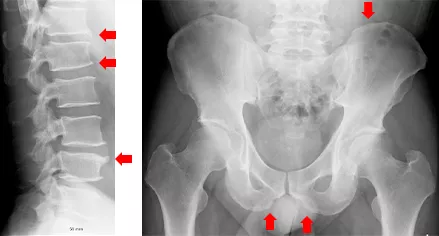

脊椎関節炎を疑い単純X線腰椎側面および骨盤正面撮影(写真4)を行った。

単純X線では仙腸関節の明らかな骨びらんは明らかではなかったが、内転筋や臀部筋の付着部の”けば立ったcalcification像”がみられ脊椎関節炎が疑われた。その後仙腸関節MRI(斜位冠状断 T1強調画像およびSTIR撮影)を行ったところ、左仙腸関節にT1強調画像でlow、STIR画像でHighの活動性仙腸関節炎をみとめ、T1強調画像では右仙腸関節に骨びらんもみとめられた(写真5)。

写真4 単純X線 腰椎側面像 骨盤正面像

Non-marginalおよびMarginal靭帯骨棘が混在(左)

仙腸関節 Grade 1両側 骨盤・恥骨周囲に毛ば立ったcalcificationあり(右)